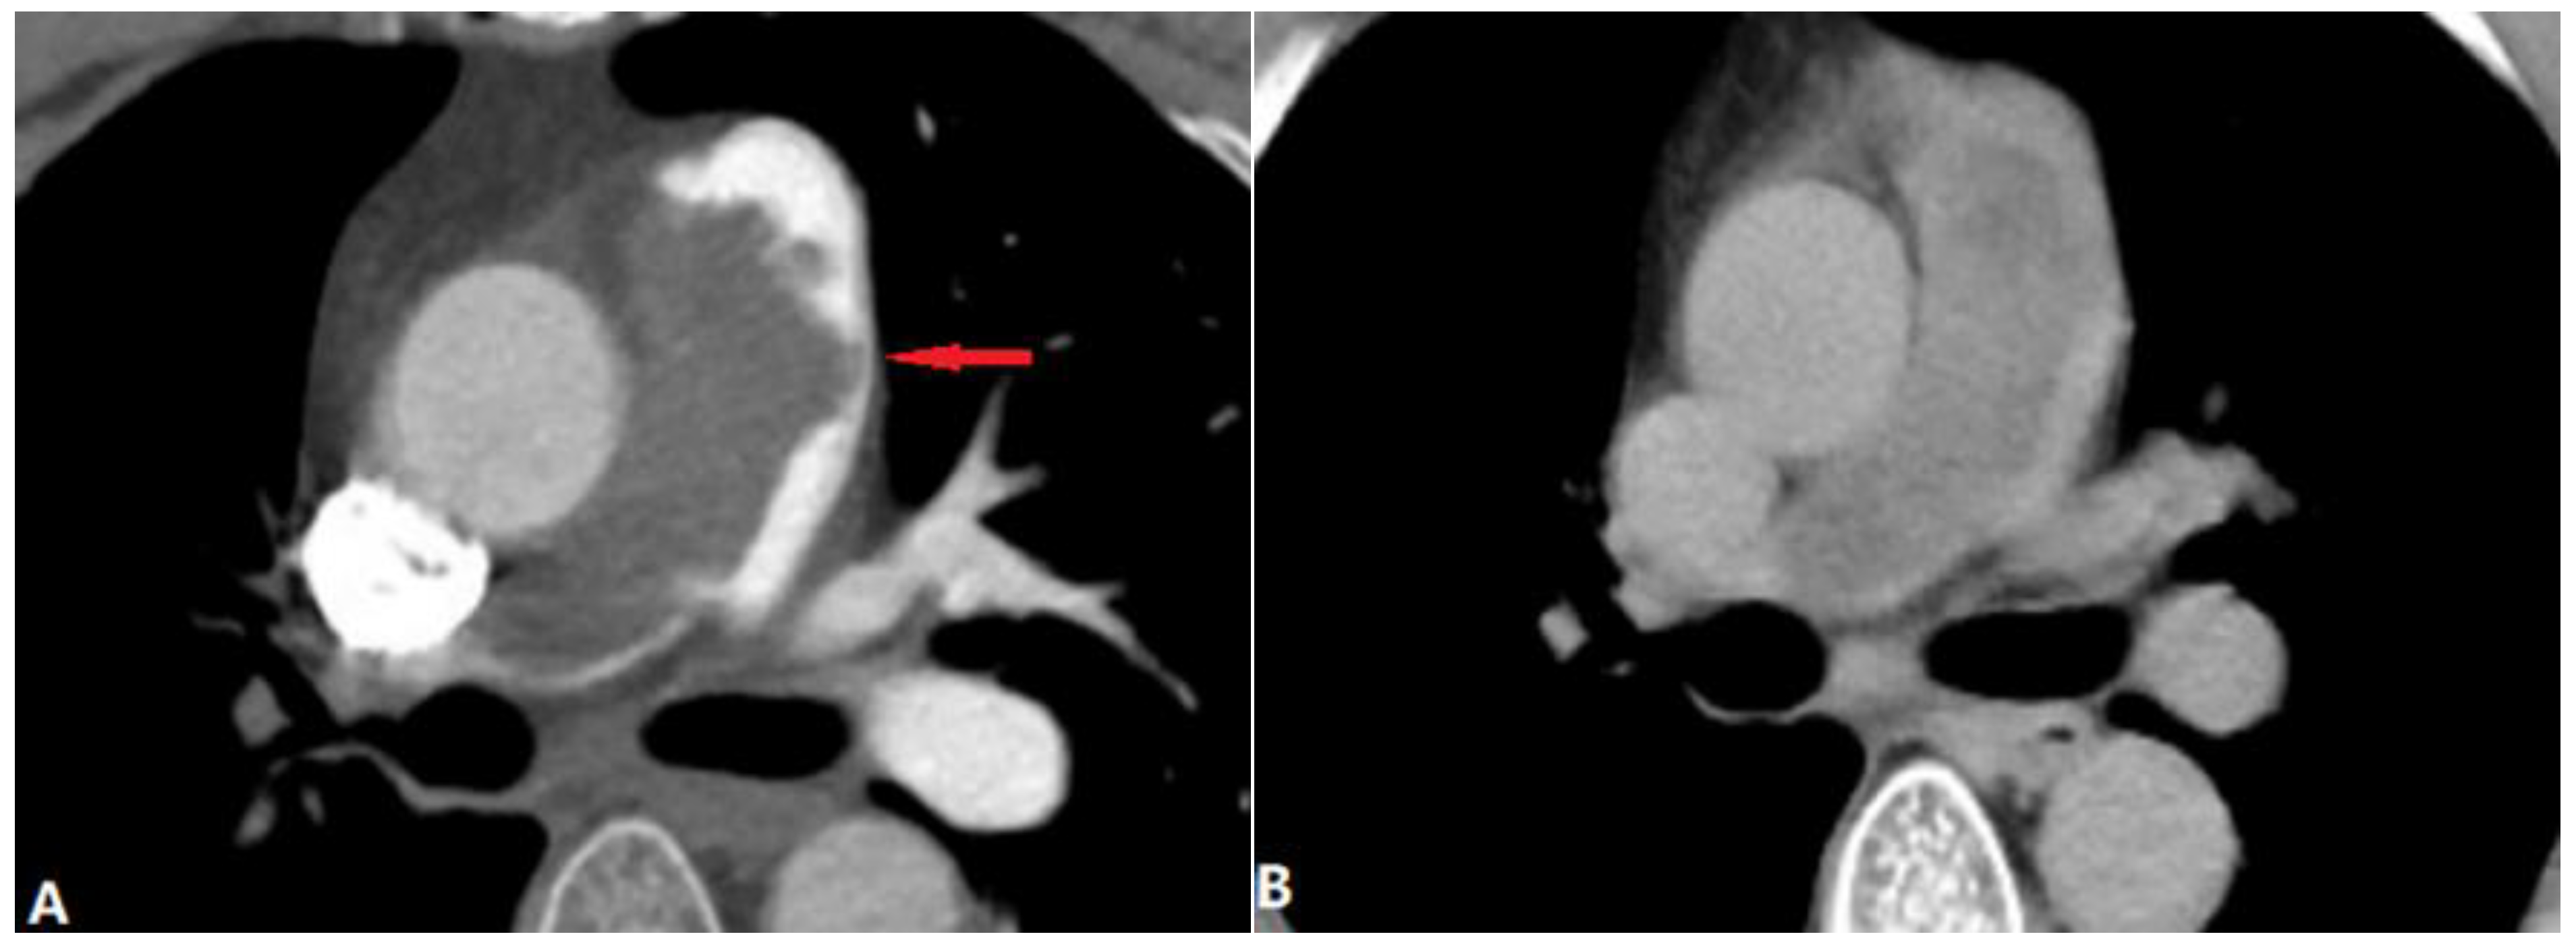

4.1.6. Pulmonary Artery Sarcoma

4.2. Vessel Wall Lesions